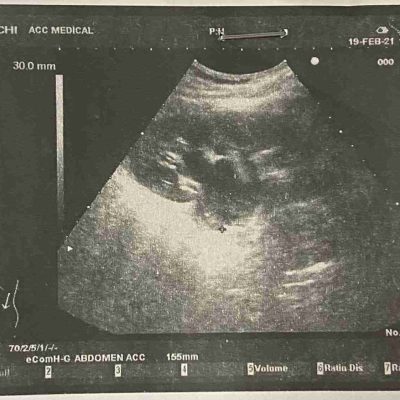

Лапароскопічне видалення вузла глибокого інфільтративного ендометріозу, уретеролізіс лівого сечоводу, видалення двобічних єндометріом.